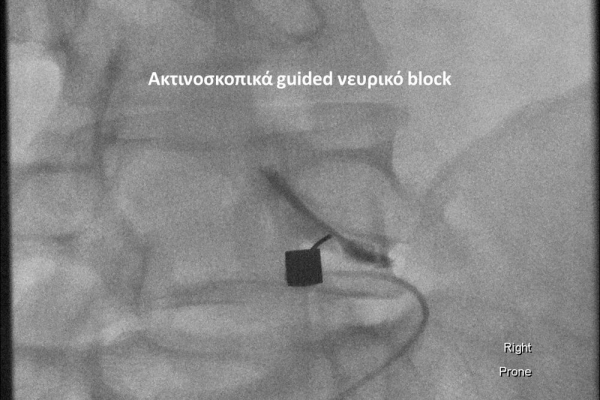

Με την βοήθεια της επεμβατικής ακτινολογίας είναι δυνατόν να πραγματοποιηθούν διαφορες ενέσιμες τεχνικές που αποσκοπούν στη μείωση του μυοσκελετικού πόνου, την ενίσχυση της αποτελεσματικότητας της φυσιοθεραπείας και την επιτάχυνση της διαδικασίας επούλωσης. Οι τεχνικές αυτές περιλαμβάνουν την κατευθυνόμενη έγχυση φαρμάκων ή πραγματοποίηση θεραπευτικών χειρισμών ακριβώς στη θέση τηςπαθολογία. Ετσι εξασφαλιζεται η μέγιστη αποτελεσματικότητα ( έως 95% κατά περίπτωση) και ασφάλεια σε σχέση με τυφλούς χειρισμούς χωρίς ακτινολογική καθοδήγηση.